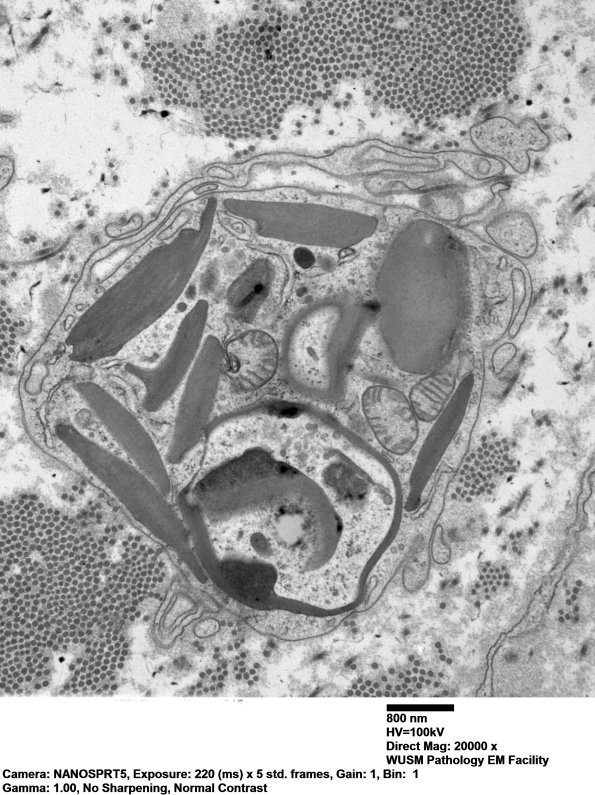

Residua of large myelinated axons are often identified by pi granule tombstones.